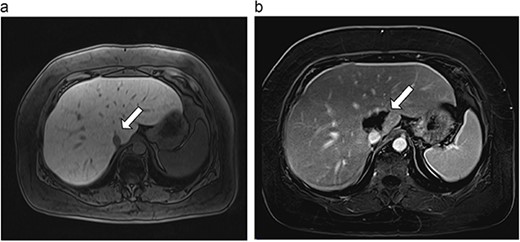

(a) Pre-ablation MRI demonstrating 15 mm lesion in caudate lobe of liver (image degraded by motion artifact). (b) Post-ablation MRI (20 days postoperatively) demonstrating 35 mm complete ablation of caudate lesion (image degraded by motion artifact).

| 2 (4a,b) | 67, M | Colon adenocarcinoma | 8 cycles capecitabine and oxaliplatin | 6 | Laparoscopic microwave ablation | 15 | 35 | 20 | 6 | No |